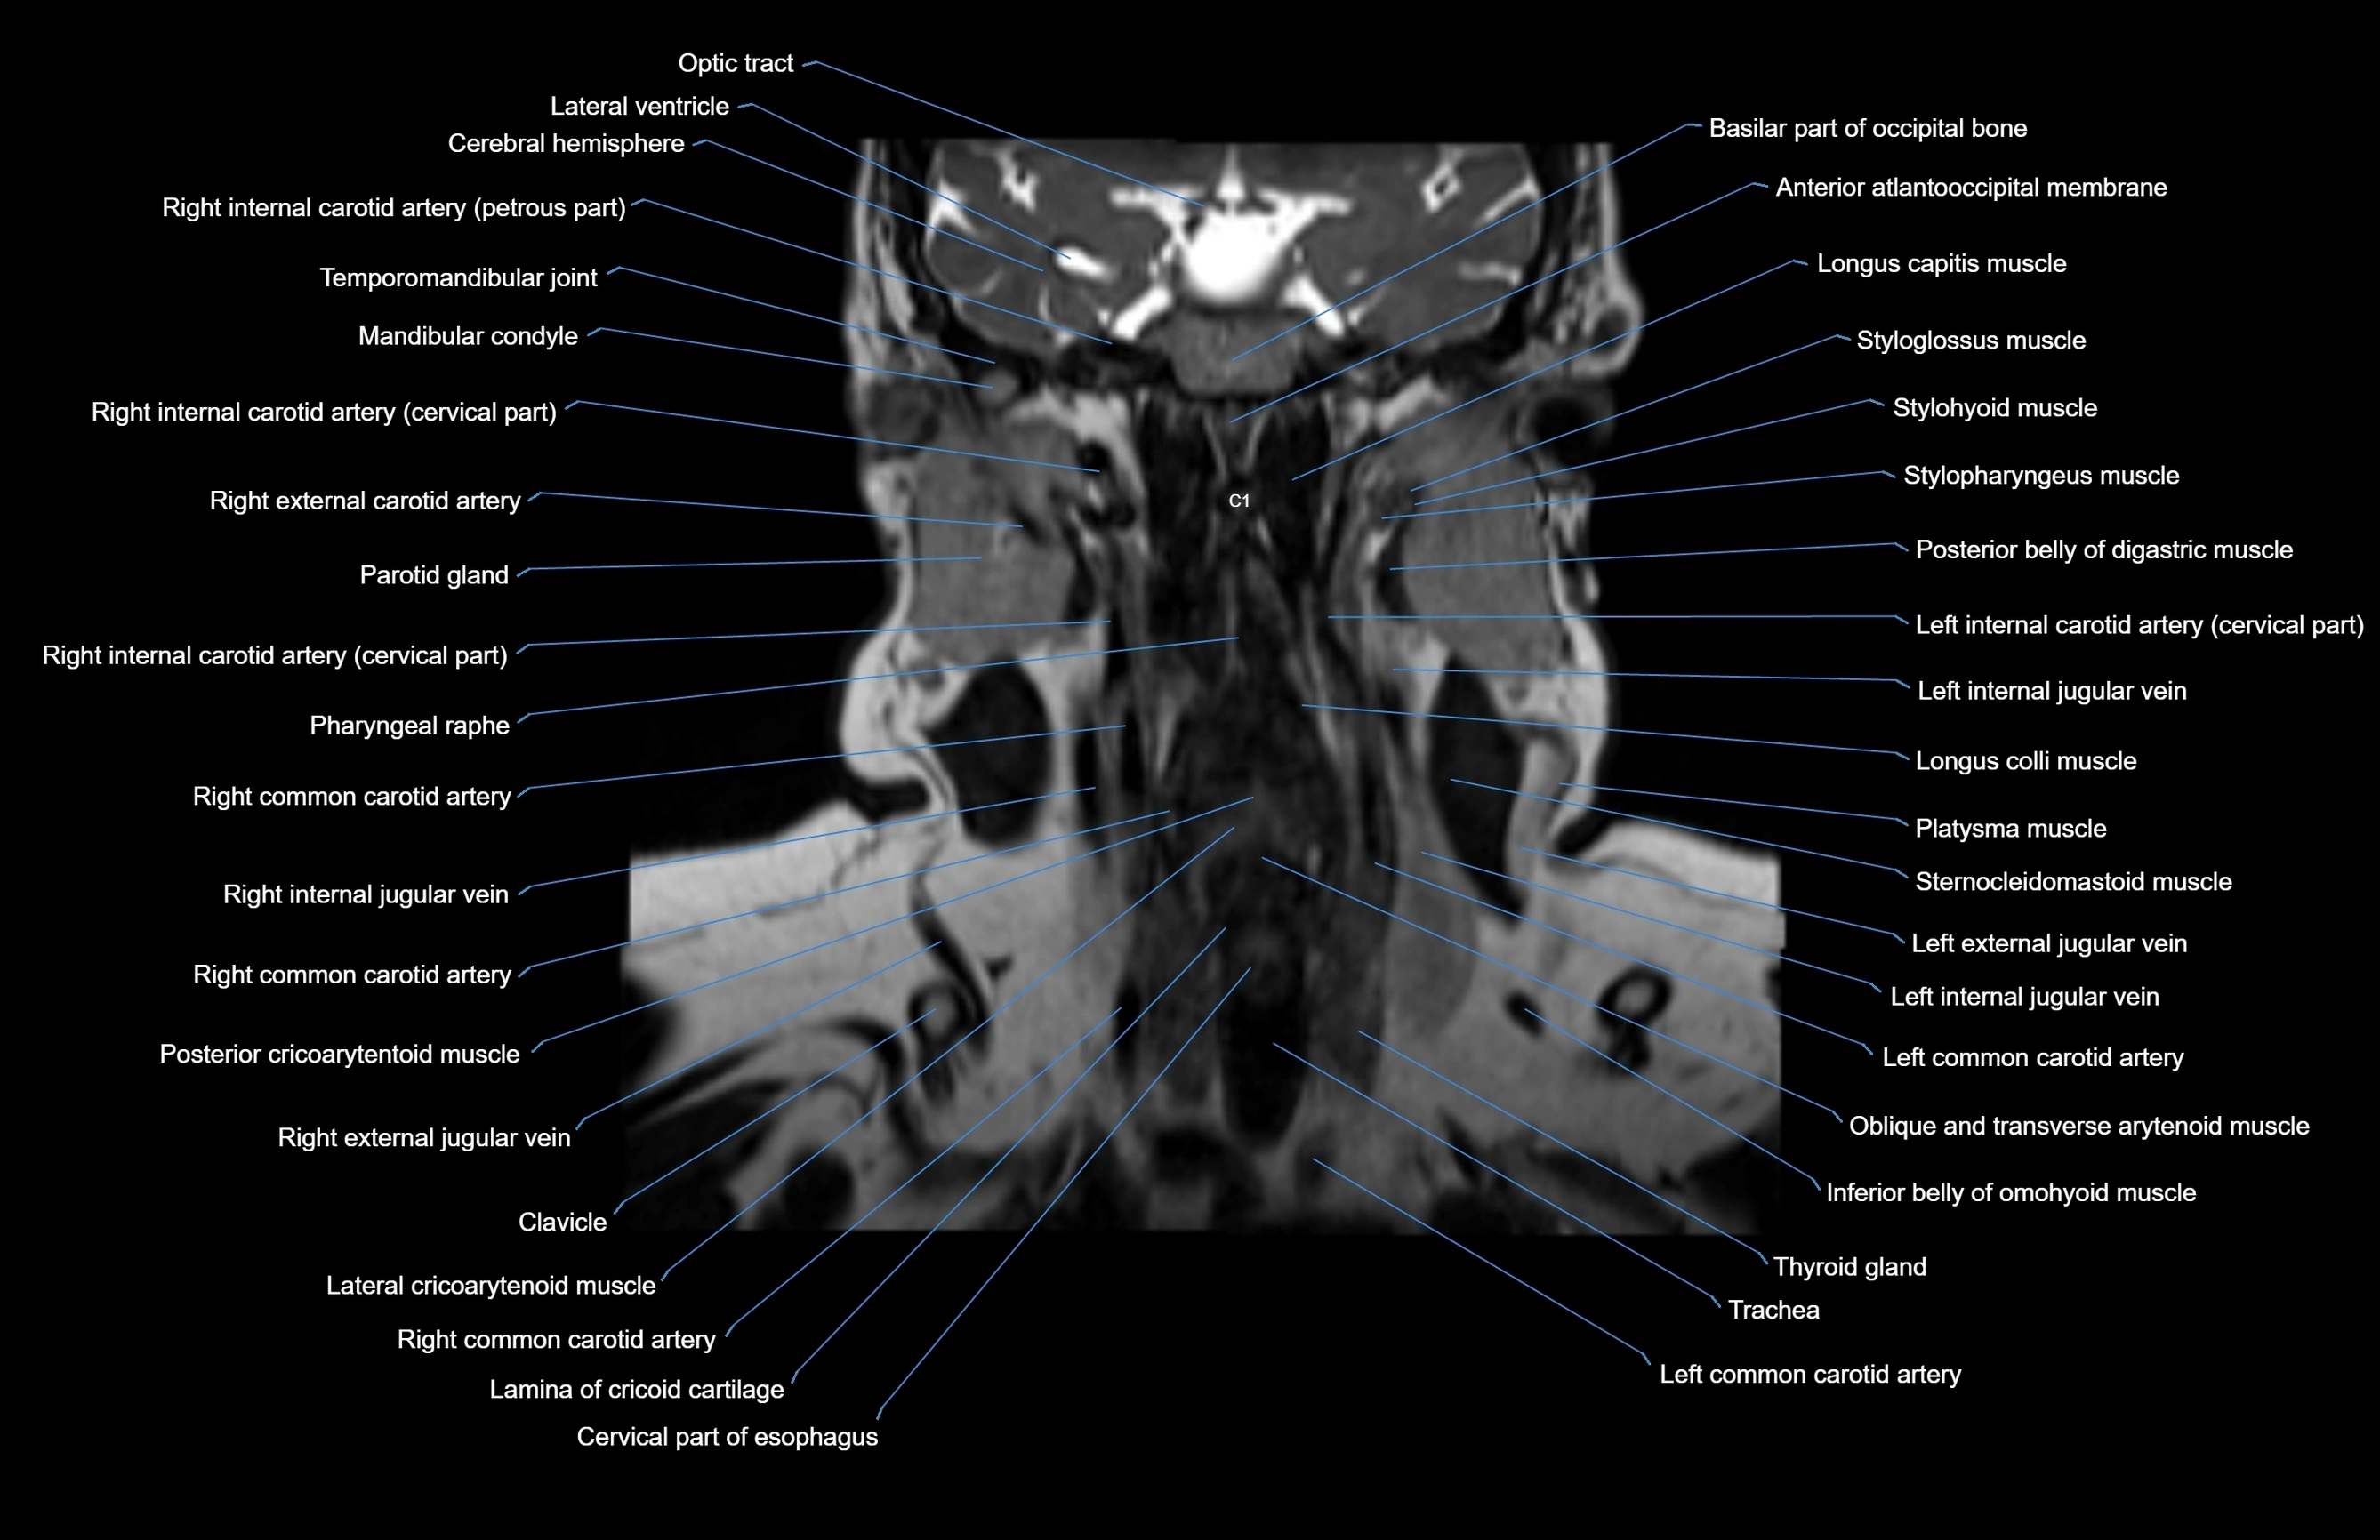

MRI images